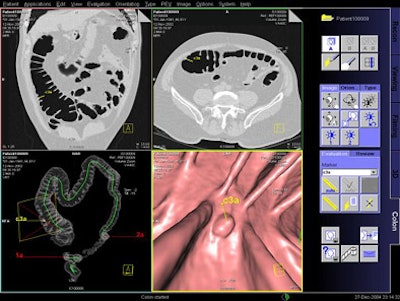

| Above, Siemens investigational VC CAD system. A marker ("c3a") is visible in the endoluminal view (lower right) representing a lesion proposed by the CAD system for physician review. The "c" indicates that it was automatically located. The other two markers (1a and 2a), also visible in the global view at lower left, were placed by the physician during the first read. The marker is highlighted in yellow because it is the one being reviewed. Images courtesy of Dr. Luca Bogoni. |